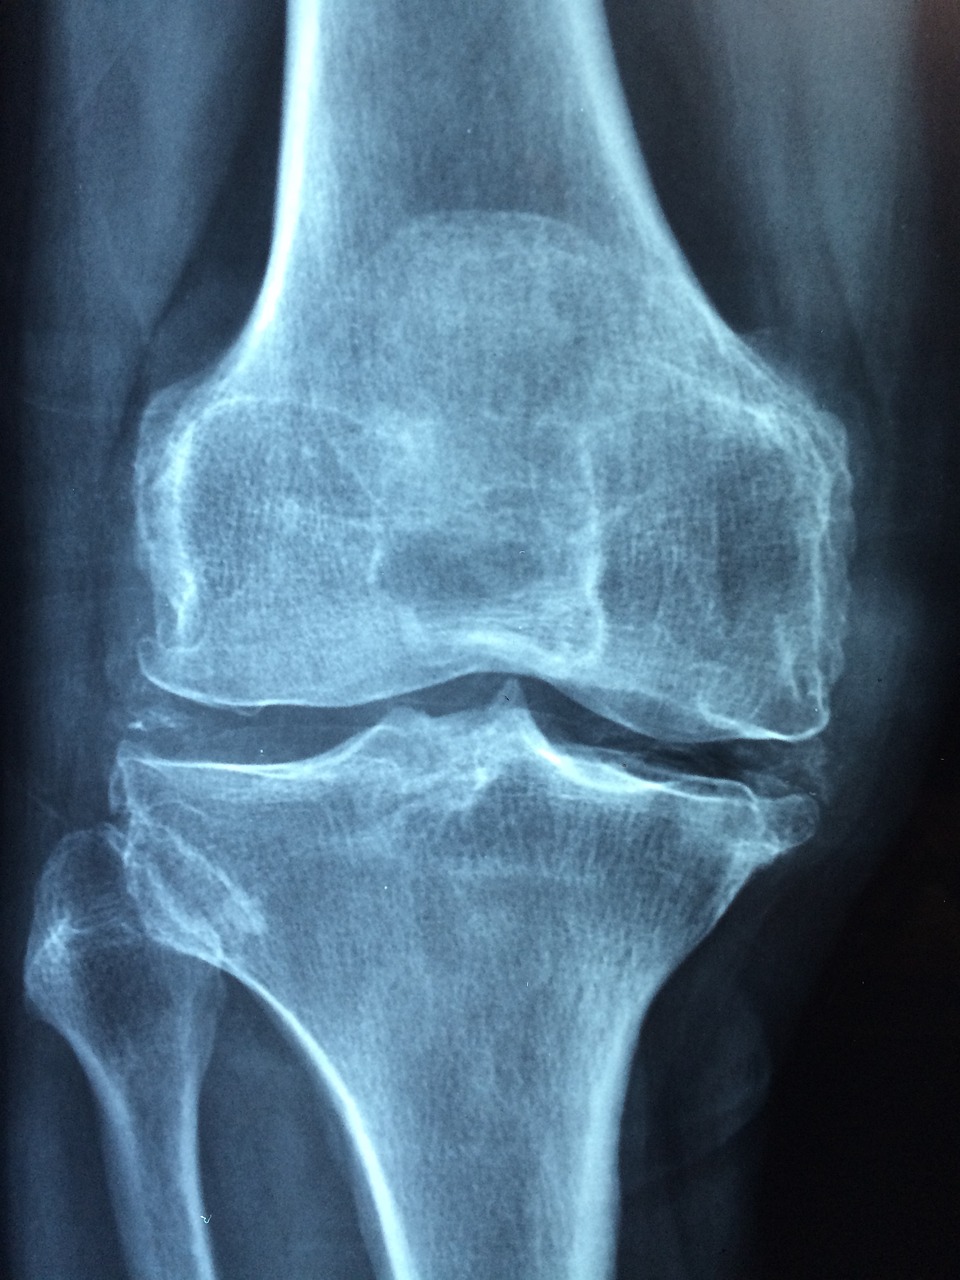

하지만 나이가 들면서 안타깝게도 낡은 뼈를 처리하는 파골세포의 활동은 빨라지는 반면, 새 뼈를 만들어 주는 조골세포의 속도가 느려지며, 숫자 또한 감소하는 일이 일어납니다. 그로 인해 골량이 줄어들게 되고 뼈에 구멍이 생기는 골다공증이 발생하게 되는 것입니다.

이렇게 골다공증이 발생하면 우리는 작은 충격에도 뼈가 부러지게 되는 것입니다. 골다공증성 골절은 뼈가 약해지는 부위에서 주로 발생하게 되며, 5-60대 여성에게 흔히 발생하는 골절로는 손목 골절이 있습니다. 골다공증이 심각할 경우, 기침만 해도 뼈가 부러질 수 있습니다.

보통 -1.0까지는 정상으로 간주하며, -2.5까지는 골감소증, -2.5보다 낮을 경우에는 골다공증으로 진단합니다.